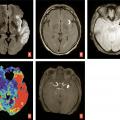

L’IRM est l’examen recommandé en France, si le plateau technique le permet sans retarder la prise en charge, et en dehors des contre-indications. Elle a une excellente sensibilité et spécificité pour détecter l’ischémie cérébrale aiguë. Un protocole standardisé est réalisable en moins de 10 minutes sans retarder la décision thérapeutique3 avec quatre séquences clés (– la séquence de diffusion pour détecter des lésions ischémiques récentes, en hypersignal avec baisse du coefficient apparent de diffusion, traduisant la restriction des mouvements des molécules d’eau secondaire à l’œdème cytotoxique. Bien que plus sensible que la tomodensitométrie, de rares faux négatifs peuvent s’observer en séquence diffusion en cas de lésion de petite taille, notamment de la fosse postérieure, d’examen très précoce ou de déficit transitoire ;

– la séquence de susceptibilité magnétique (T2* ou SWI) pour détecter un hématome,1 des séquelles hématiques ou une transformation hémorragique de lésions ischémiques, en particulier après traitement de recanalisation. Le thrombus artériel apparaît en hyposignal artériel linéaire ou curviligne en T2*, dont la sensibilité varie selon la composition du caillot, sa taille et le type de séquence utilisée ;

– la séquence FLAIR, qui permet d’apprécier l’étendue de la leucopathie vasculaire et les séquelles d’infarctus anciens, de dater l’infarctus (classiquement non visible avant 3 heures),1 de rechercher des hypersignaux vasculaires, en rapport avec des ralentissements vasculaires dans les artères collatérales en aval de l’occlusion ;

– l’angiographie par résonance magnétique (angio-IRM) 3D temps de vol du polygone de Willis (sans injection) afin de rechercher une occlusion ou une sténose des artères intracrâniennes. La séquence de perfusion T2* peut également être réalisée. Comme en tomodensitométrie, elle permet d’apprécier le risque d’extension de l’infarctus (« mismatch » perfusion-diffusion) et de décider d’un traitement de recanalisation dans des situations particulières (heure de début des symptômes inconnue, délai tardif)1 [